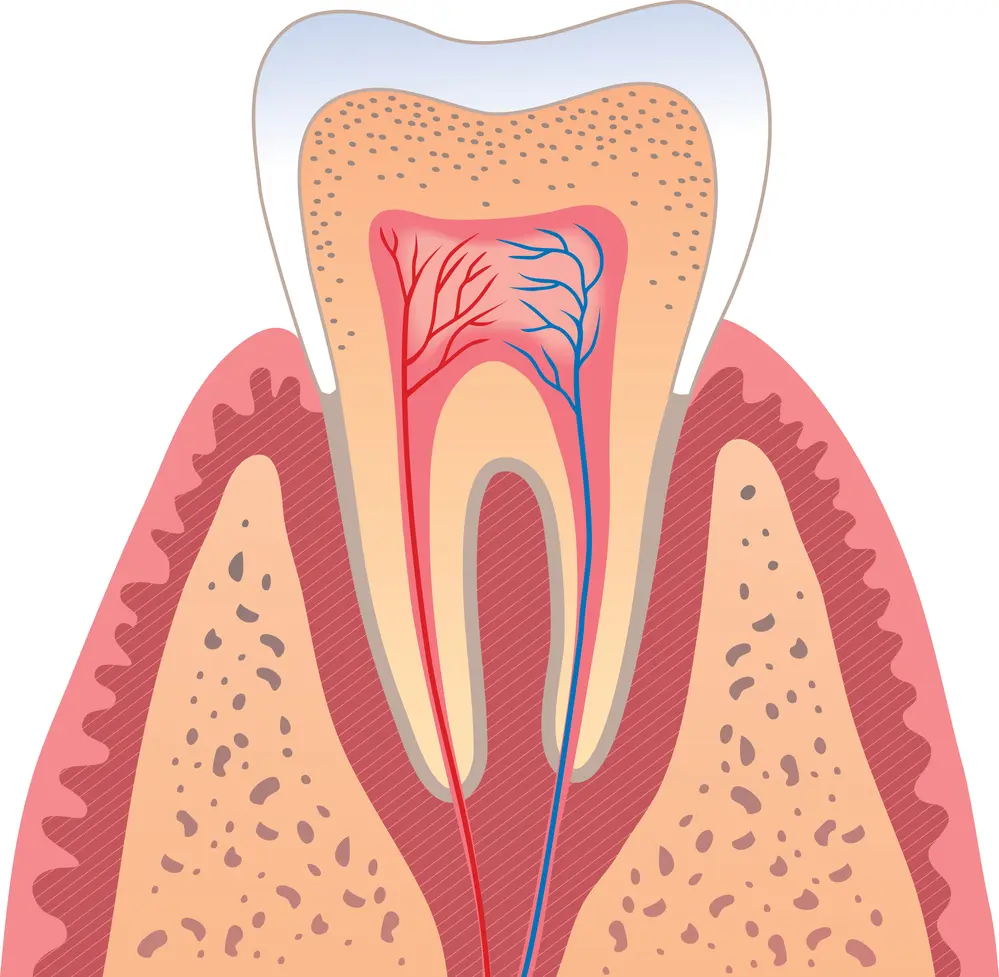

Los dientes, estructuras duras compuestas principalmente de calcio y fósforo, se insertan en los alvéolos de los huesos maxilares mediante el ligamento periodontal. Cada diente se divide en partes visibles e invisibles:

- Corona: La parte visible del diente, dura y resistente, cuya forma determina su función (cortar, moler).

- Esmalte: El tejido más duro del cuerpo humano, recubre la corona, es traslúcido e insensible al dolor.

- Raíz: La parte del diente insertada en el hueso, no visible, y que puede tener de una a tres raíces según el tipo de diente.

- Dentina: Capa situada debajo del esmalte, responsable del color del diente, sensible a las temperaturas.

- Pulpa: Tejido blando en el interior del diente, contiene nervios y vasos sanguíneos, vital para la sensibilidad y nutrición del diente.

La cavidad bucal cumple funciones vitales como la alimentación, el habla y la expresión facial. La anatomía dental estudia la estructura, morfología, función y movimiento de los dientes, individual y colectivamente. La comprensión de las partes de un diente es esencial:

- Corona: Su forma determina la función del diente.

- Esmalte: Tejido duro, frágil y no regenerativo.

- Raíz: Parte no visible, insertada en el hueso.

- Dentina: Sensible a las temperaturas.

- Pulpa: Tejido blando que nutre y protege el diente.

Los dientes están formados por:

- Esmalte: Tejido más duro y mineralizado del cuerpo.

- Dentina: Proporciona color y elasticidad al diente.

- Pulpa: Tejido vital para la sensibilidad y nutrición.

- Periodonto: Tejido de soporte del diente (cemento, ligamento periodontal, hueso alveolar y encía).